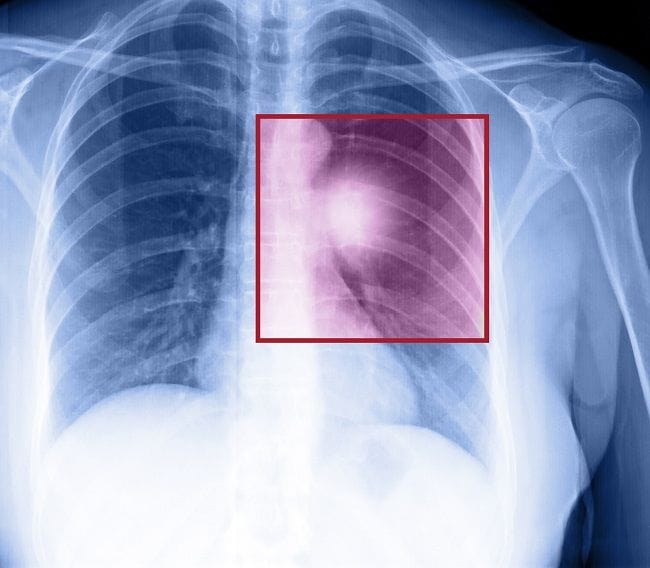

- Foto Rontgen dada, untuk melihat lokasi kelainan dan kondisi tumor di paru-paru

- CT scan atau MRI, untuk melihat ukuran dan letak tumor dengan lebih detail, serta melihat kondisi jaringan di sekitar organ paru-paru

Pemeriksaan di atas dapat membedakan tumor yang jinak atau ganas. Dari foto, tumor yang jinak biasanya berukuran kecil, memiliki bentuk dengan batas yang halus pada hasil foto, dan tidak berkembang dengan cepat ketika dilakukan pemeriksaan lanjutan.